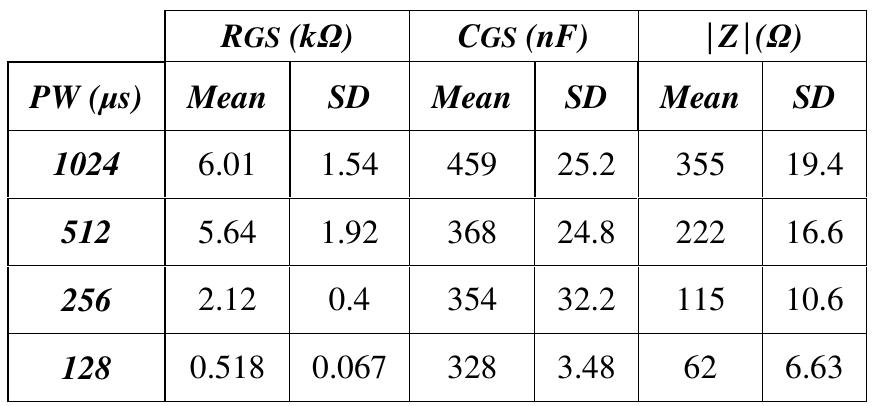

In this study, an equivalent circuit model (ECM) to simulate the Neuromuscular Electrical Stimulation (NMES) has been developed. The ECM includes all regions from the transcutaneous electrodes to the neuron cell membrane to simulate the... more